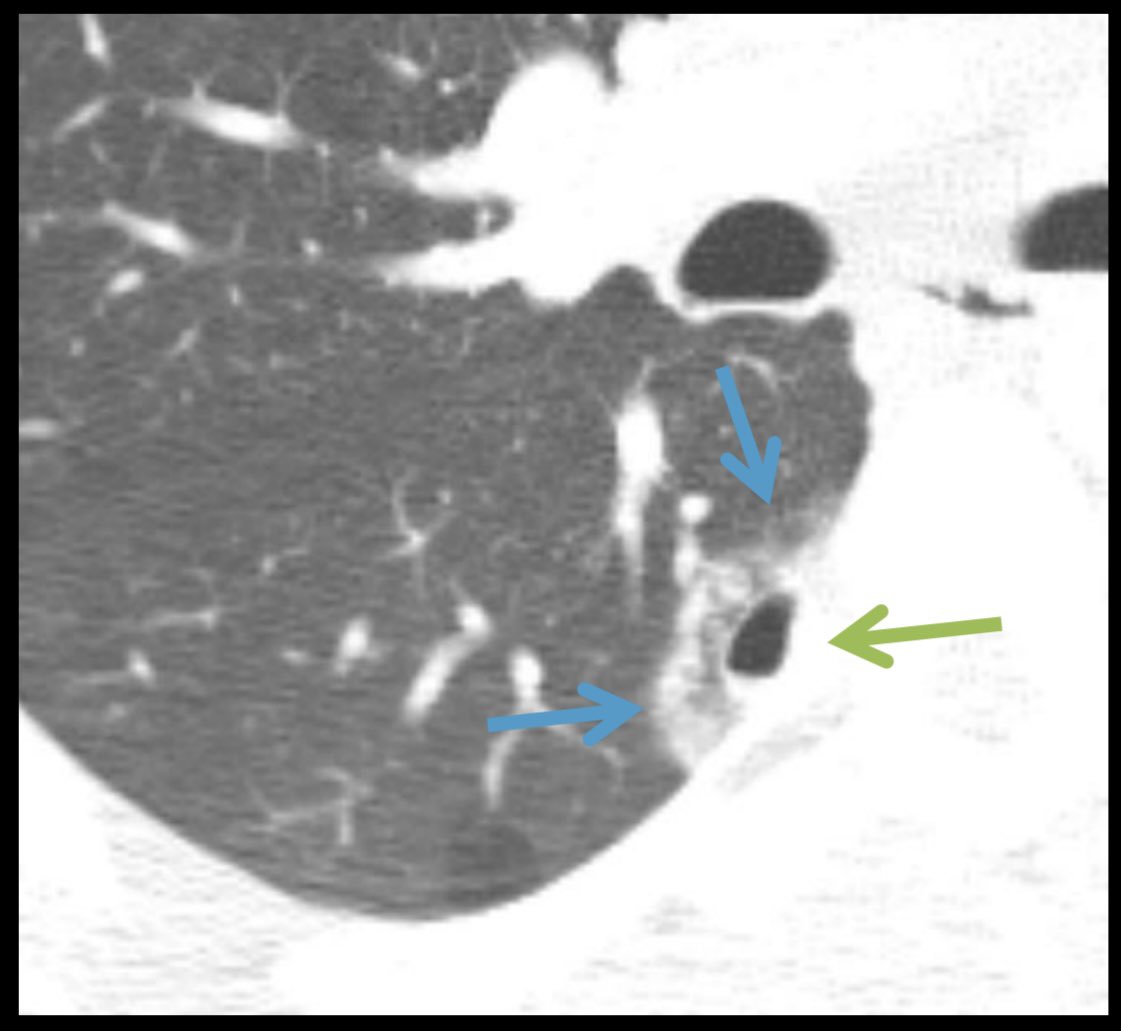

Emily B. Tsai, MD

4 years

Lung contusion and laceration in a football player 🏈